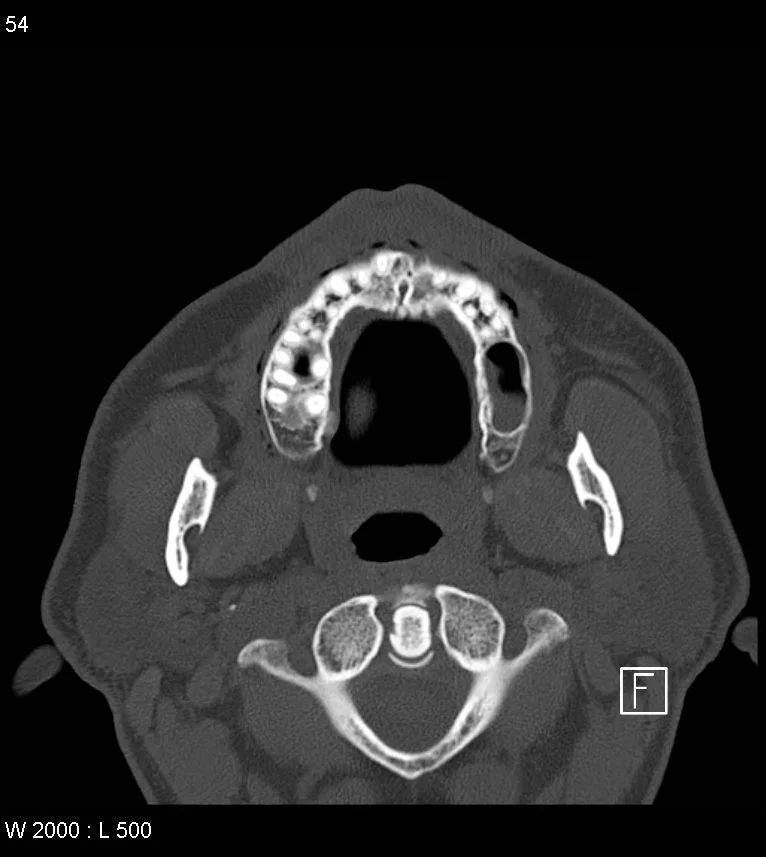

• Transverse part (seen on CT below)

• C1 lateral masses to tectorial membrane and dura

• Runs posterior to dens

• Strong and provides stability